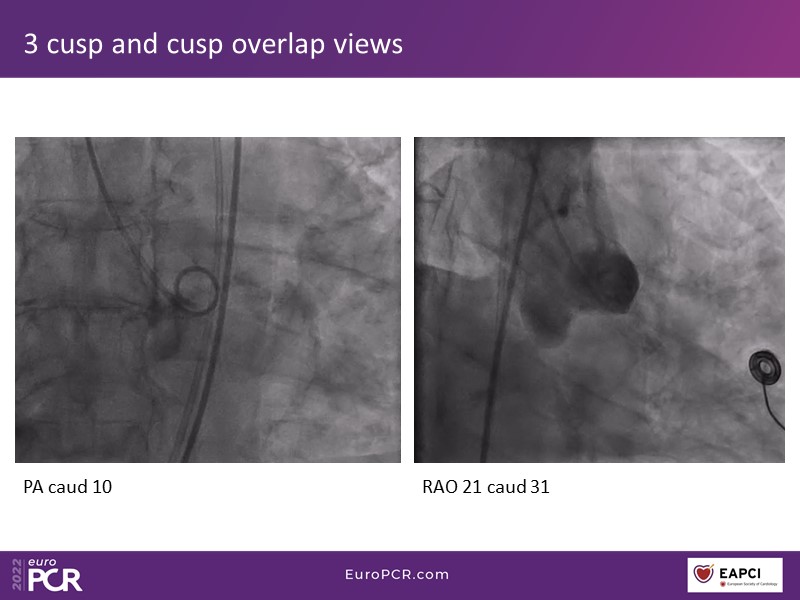

Through the presentation of real-life clinical cases, this session will allow you to discover the use of ALLEGRA for valve-in-valve TAVI, understand the management of coronary artery disease in TAVI patients, better detect when and how to protect coronary arteries during TAVI, or even learn how to perform commissural alignment with ALLEGRA.

- To better detect when and how to protect the coronary arteries during TAVI

- To learn how to perform commissural alignment with the ALLEGRA